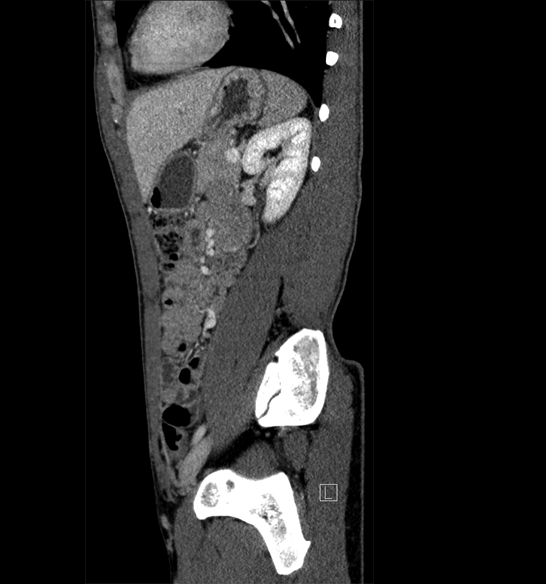

Body

Covers abdominal CT anatomy.